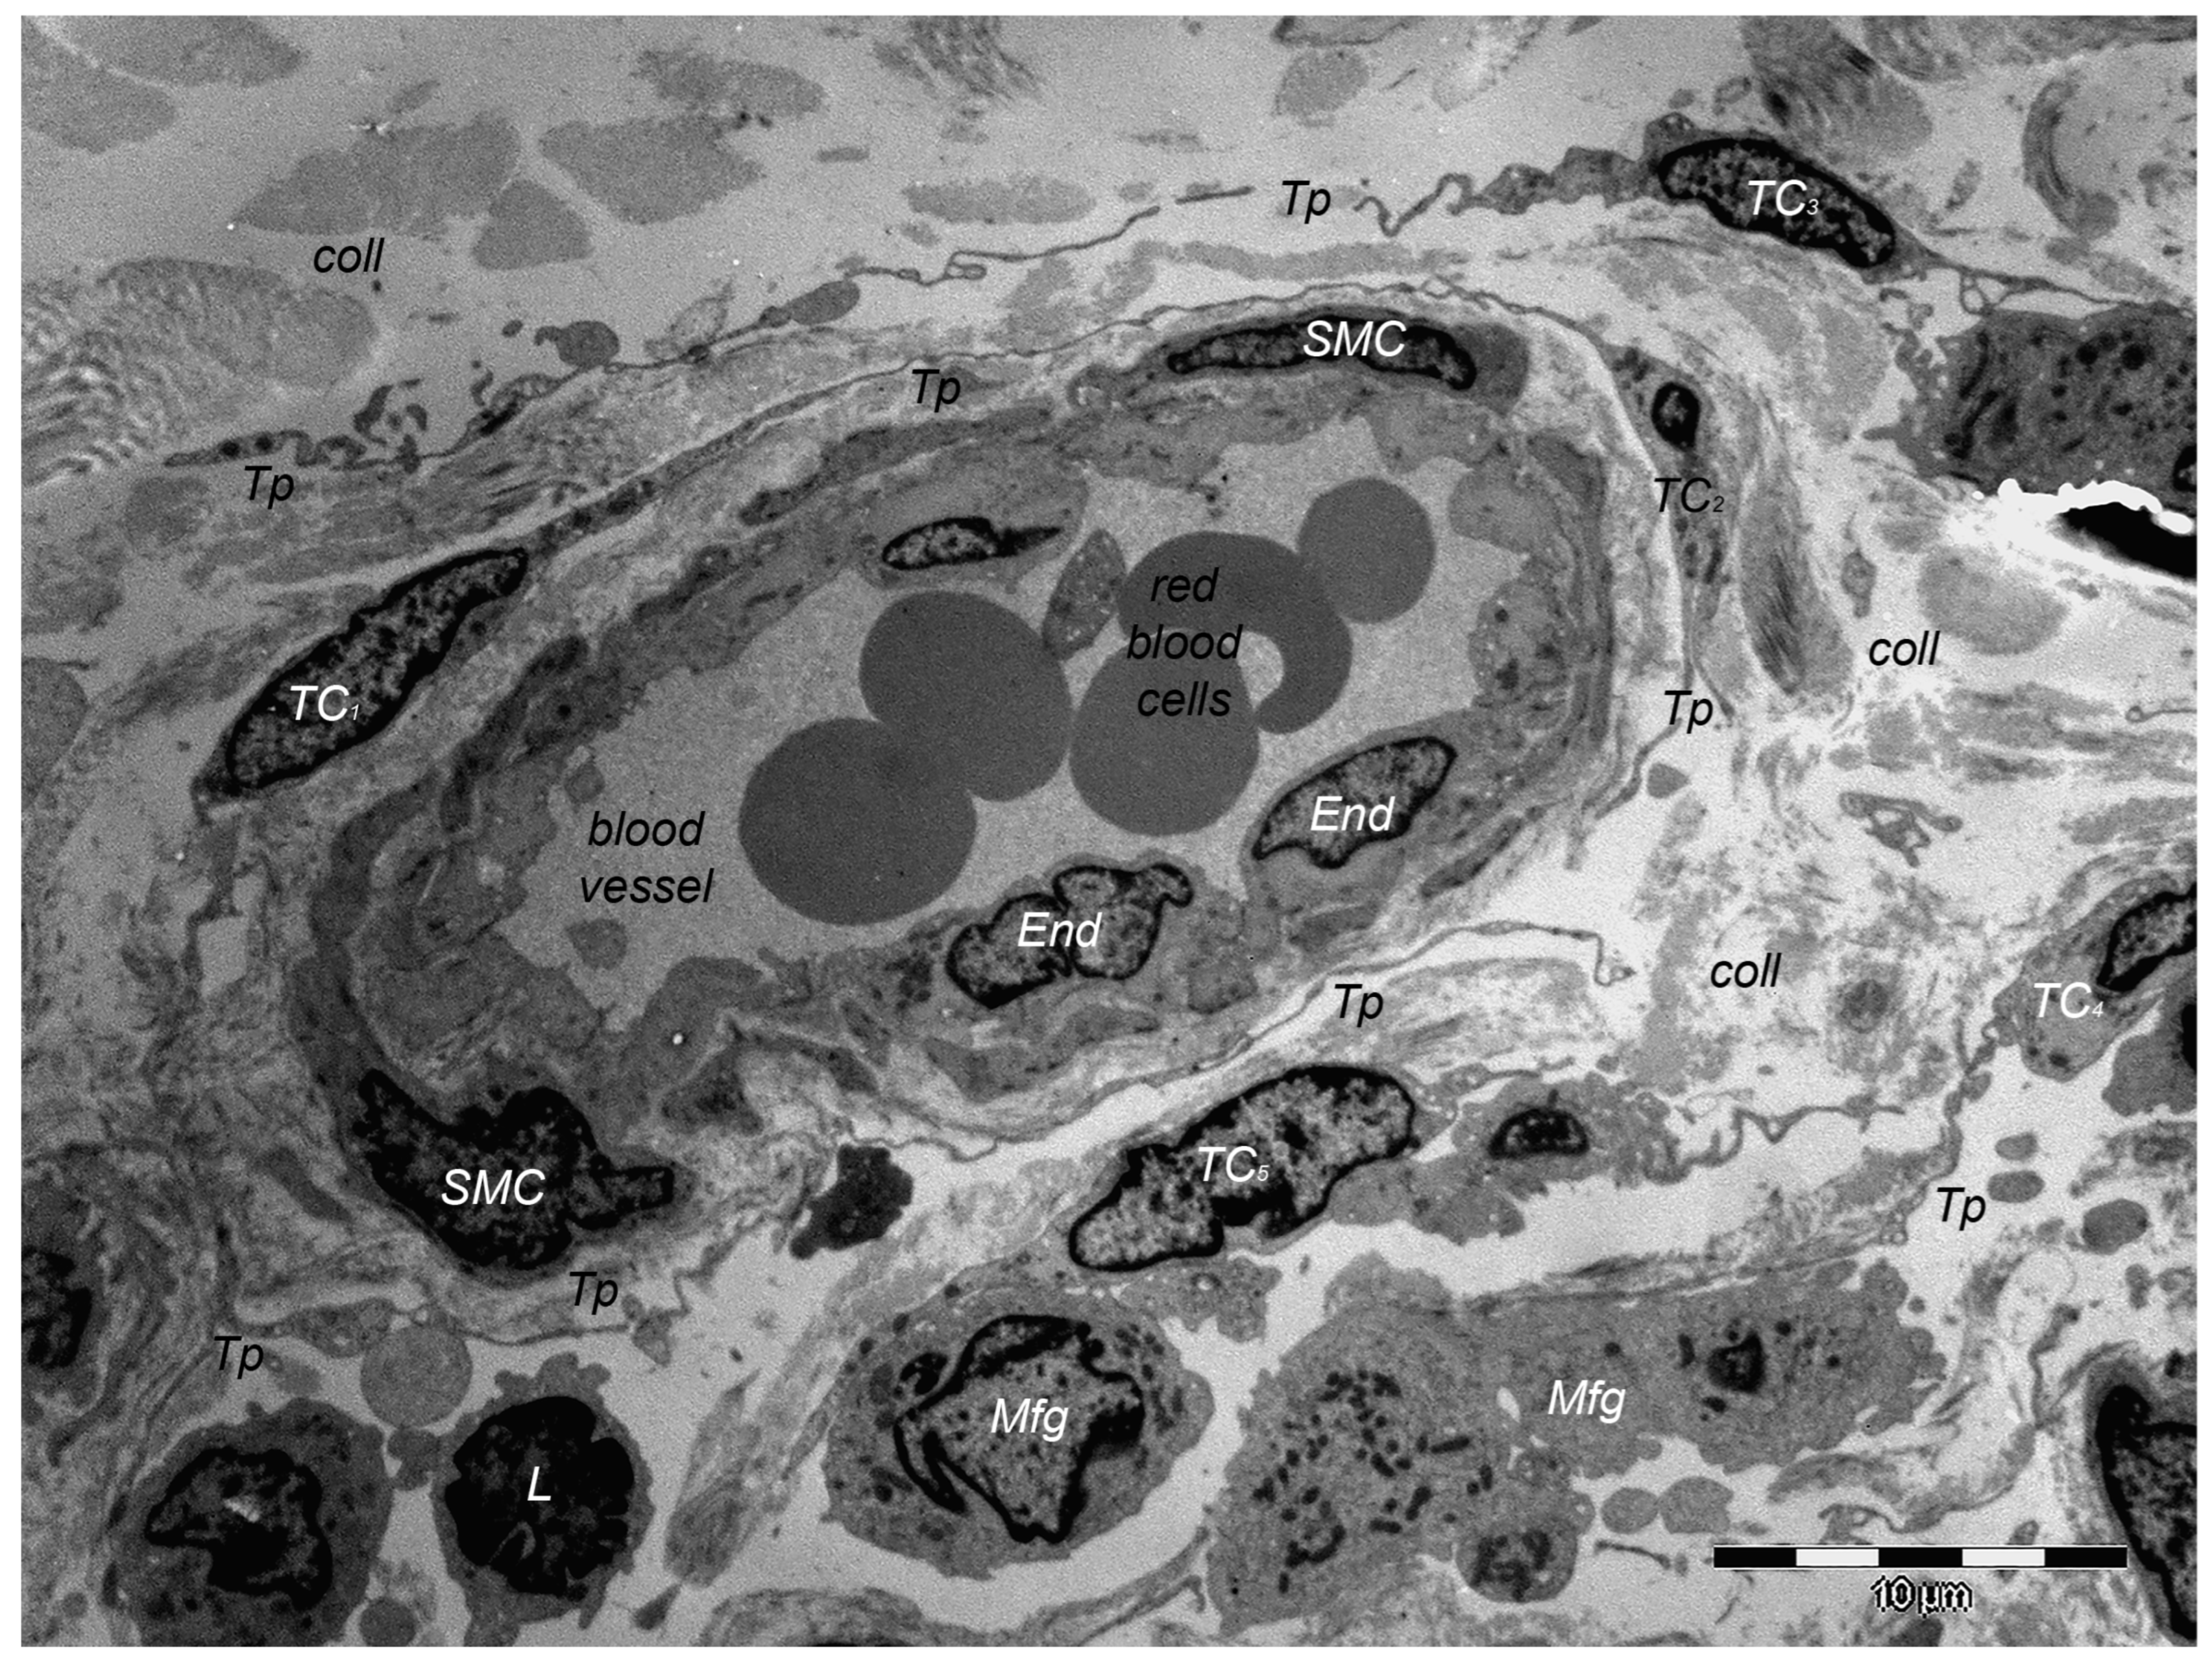

9. Dermal TCs: A Distinct Cell Population with a Promising Skin Regenerative Potential

- Rusu, M.C.; Mirancea, N.; Mănoiu, V.S.; Vâlcu, M.; Nicolescu, M.I.; Păduraru, D. Skin Telocytes. Ann. Anat.—Anat. Anz. 2012, 194, 359–367. [Google Scholar] [CrossRef] [PubMed]

- Manole, C.G.; Soare, C.; Ceafalan, L.C.; Voiculescu, V.M. Platelet-Rich Plasma in Dermatology: New Insights on the Cellular Mechanism of Skin Repair and Regeneration. Life 2023, 14, 40. [Google Scholar] [CrossRef] [PubMed]

- Wang, L.; Xiao, L.; Zhang, R.; Jin, H.; Shi, H. Ultrastructural and Immunohistochemical Characteristics of Telocytes in Human Scalp Tissue. Sci. Rep. 2020, 10, 1693. [Google Scholar] [CrossRef] [PubMed]

- Díaz-Flores, L.; Gutiérrez, R.; Pino García, M.; González, M.; Díaz-Flores, L.; Francisco Madrid, J. Telocytes as a Source of Progenitor Cells in Regeneration and Repair through Granulation Tissue. Curr. Stem Cell Res. Ther. 2016, 11, 395–403. [Google Scholar] [CrossRef]

- Díaz-Flores, L.; Gutiérrez, R.; García, M.P.; González-Gómez, M.; Rodríguez-Rodriguez, R.; Hernández-León, N.; Díaz-Flores, L.; Carrasco, J.L. Cd34+ Stromal Cells/Telocytes in Normal and Pathological Skin. Int. J. Mol. Sci. 2021, 22, 7342. [Google Scholar] [CrossRef] [PubMed]